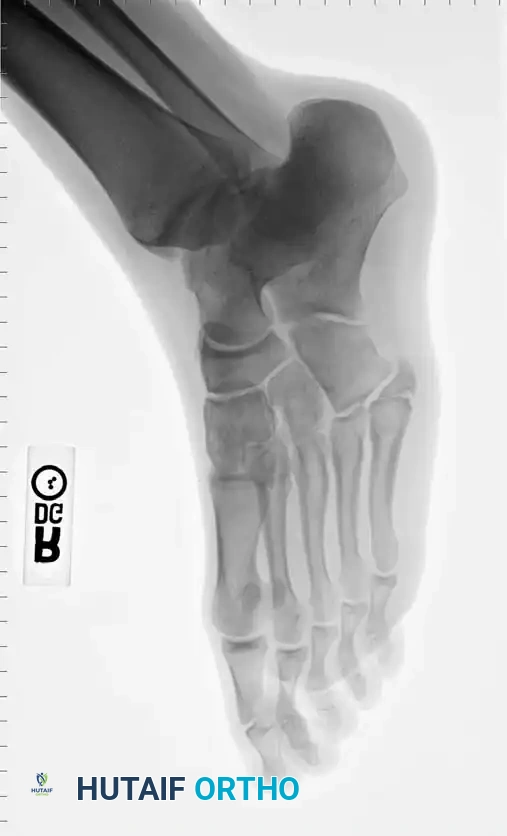

Fig. 86-45 A-C. Type IA (DeLee) fifth metatarsal fracture in a collegiate soccer player, representing an ideal candidate for early intramedullary fixation.

Fig. 86-45 A-C, Type IA (DeLee) fi fth metatarsal fracture in collegiate soccer player. D-F, After fi xation with variable pitch compression screw.

Fig. 86-45 D-F. Postoperative imaging after robust fixation utilizing a variable pitch compression screw, ensuring excellent compression across the fracture site.